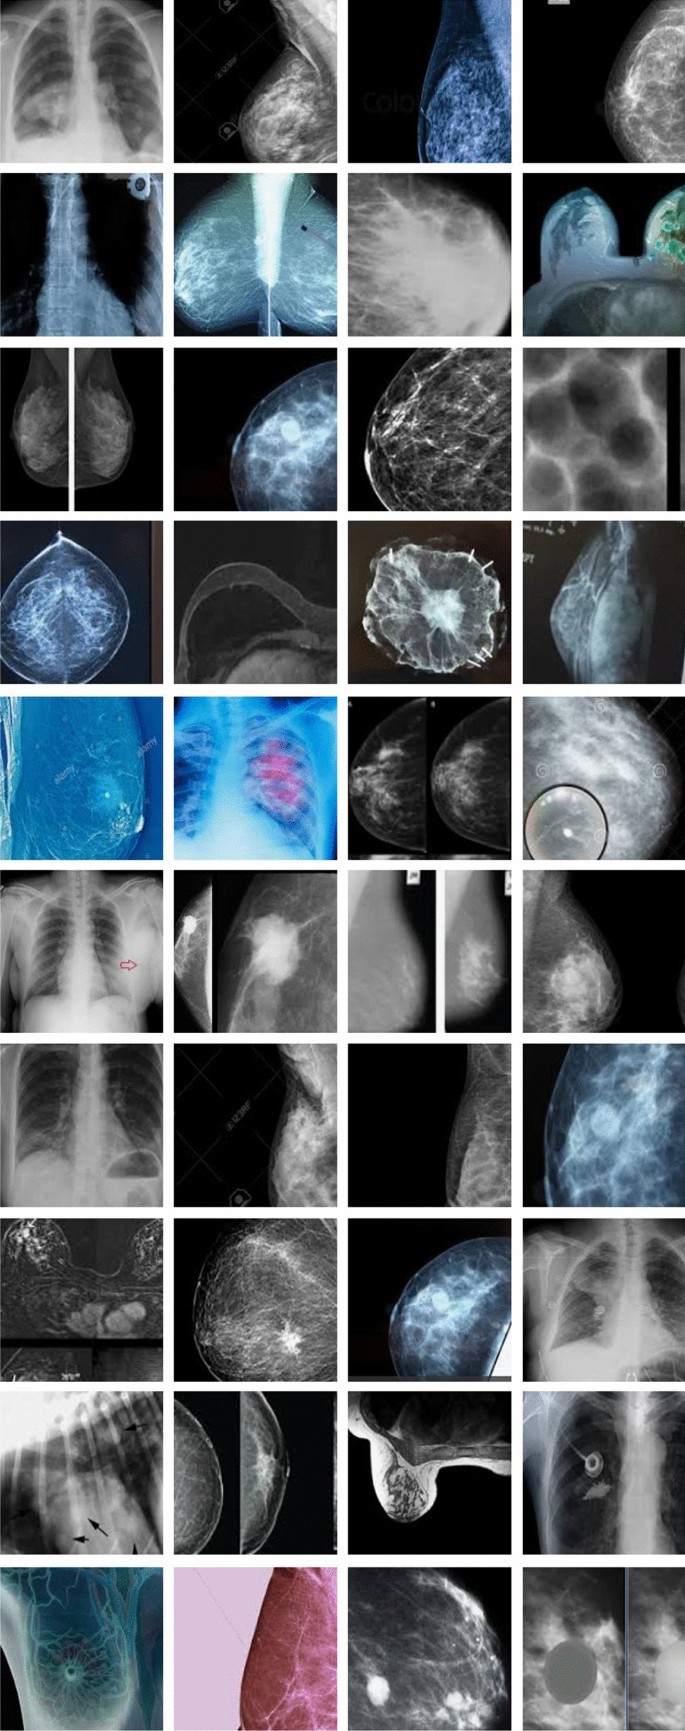

As far as we know, no fully-annotated breast cancer dataset is publicly available. Our project required significant effort to collect approximately 2.73 million breast X-ray images from 125 hospitals across our country. These X-rays, particularly from urban hospital centers, show greater clarity and detail and are properly white-balanced. We designed a specialized crawler to automate the downloading and cropping of images from these hospitals. Unlike the crawling process, the sorting and annotating process was semi-automated. This process involved recording data such as age, education, and occupation for each image. Example images are shown in Fig. 3.